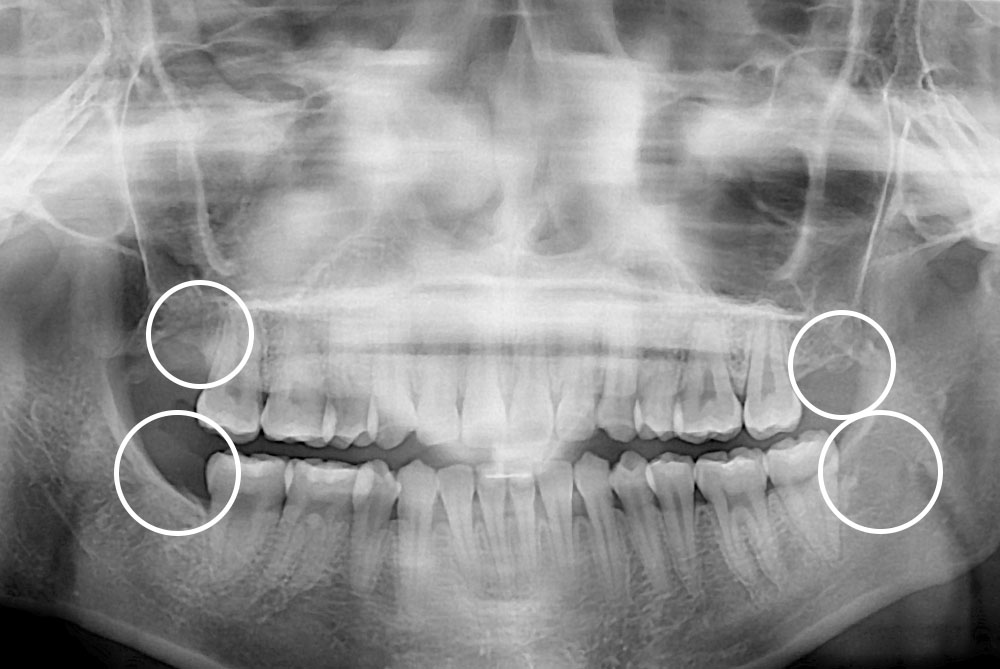

[사랑니] 매복 사랑니 발치

치료후 : 2020-06-19